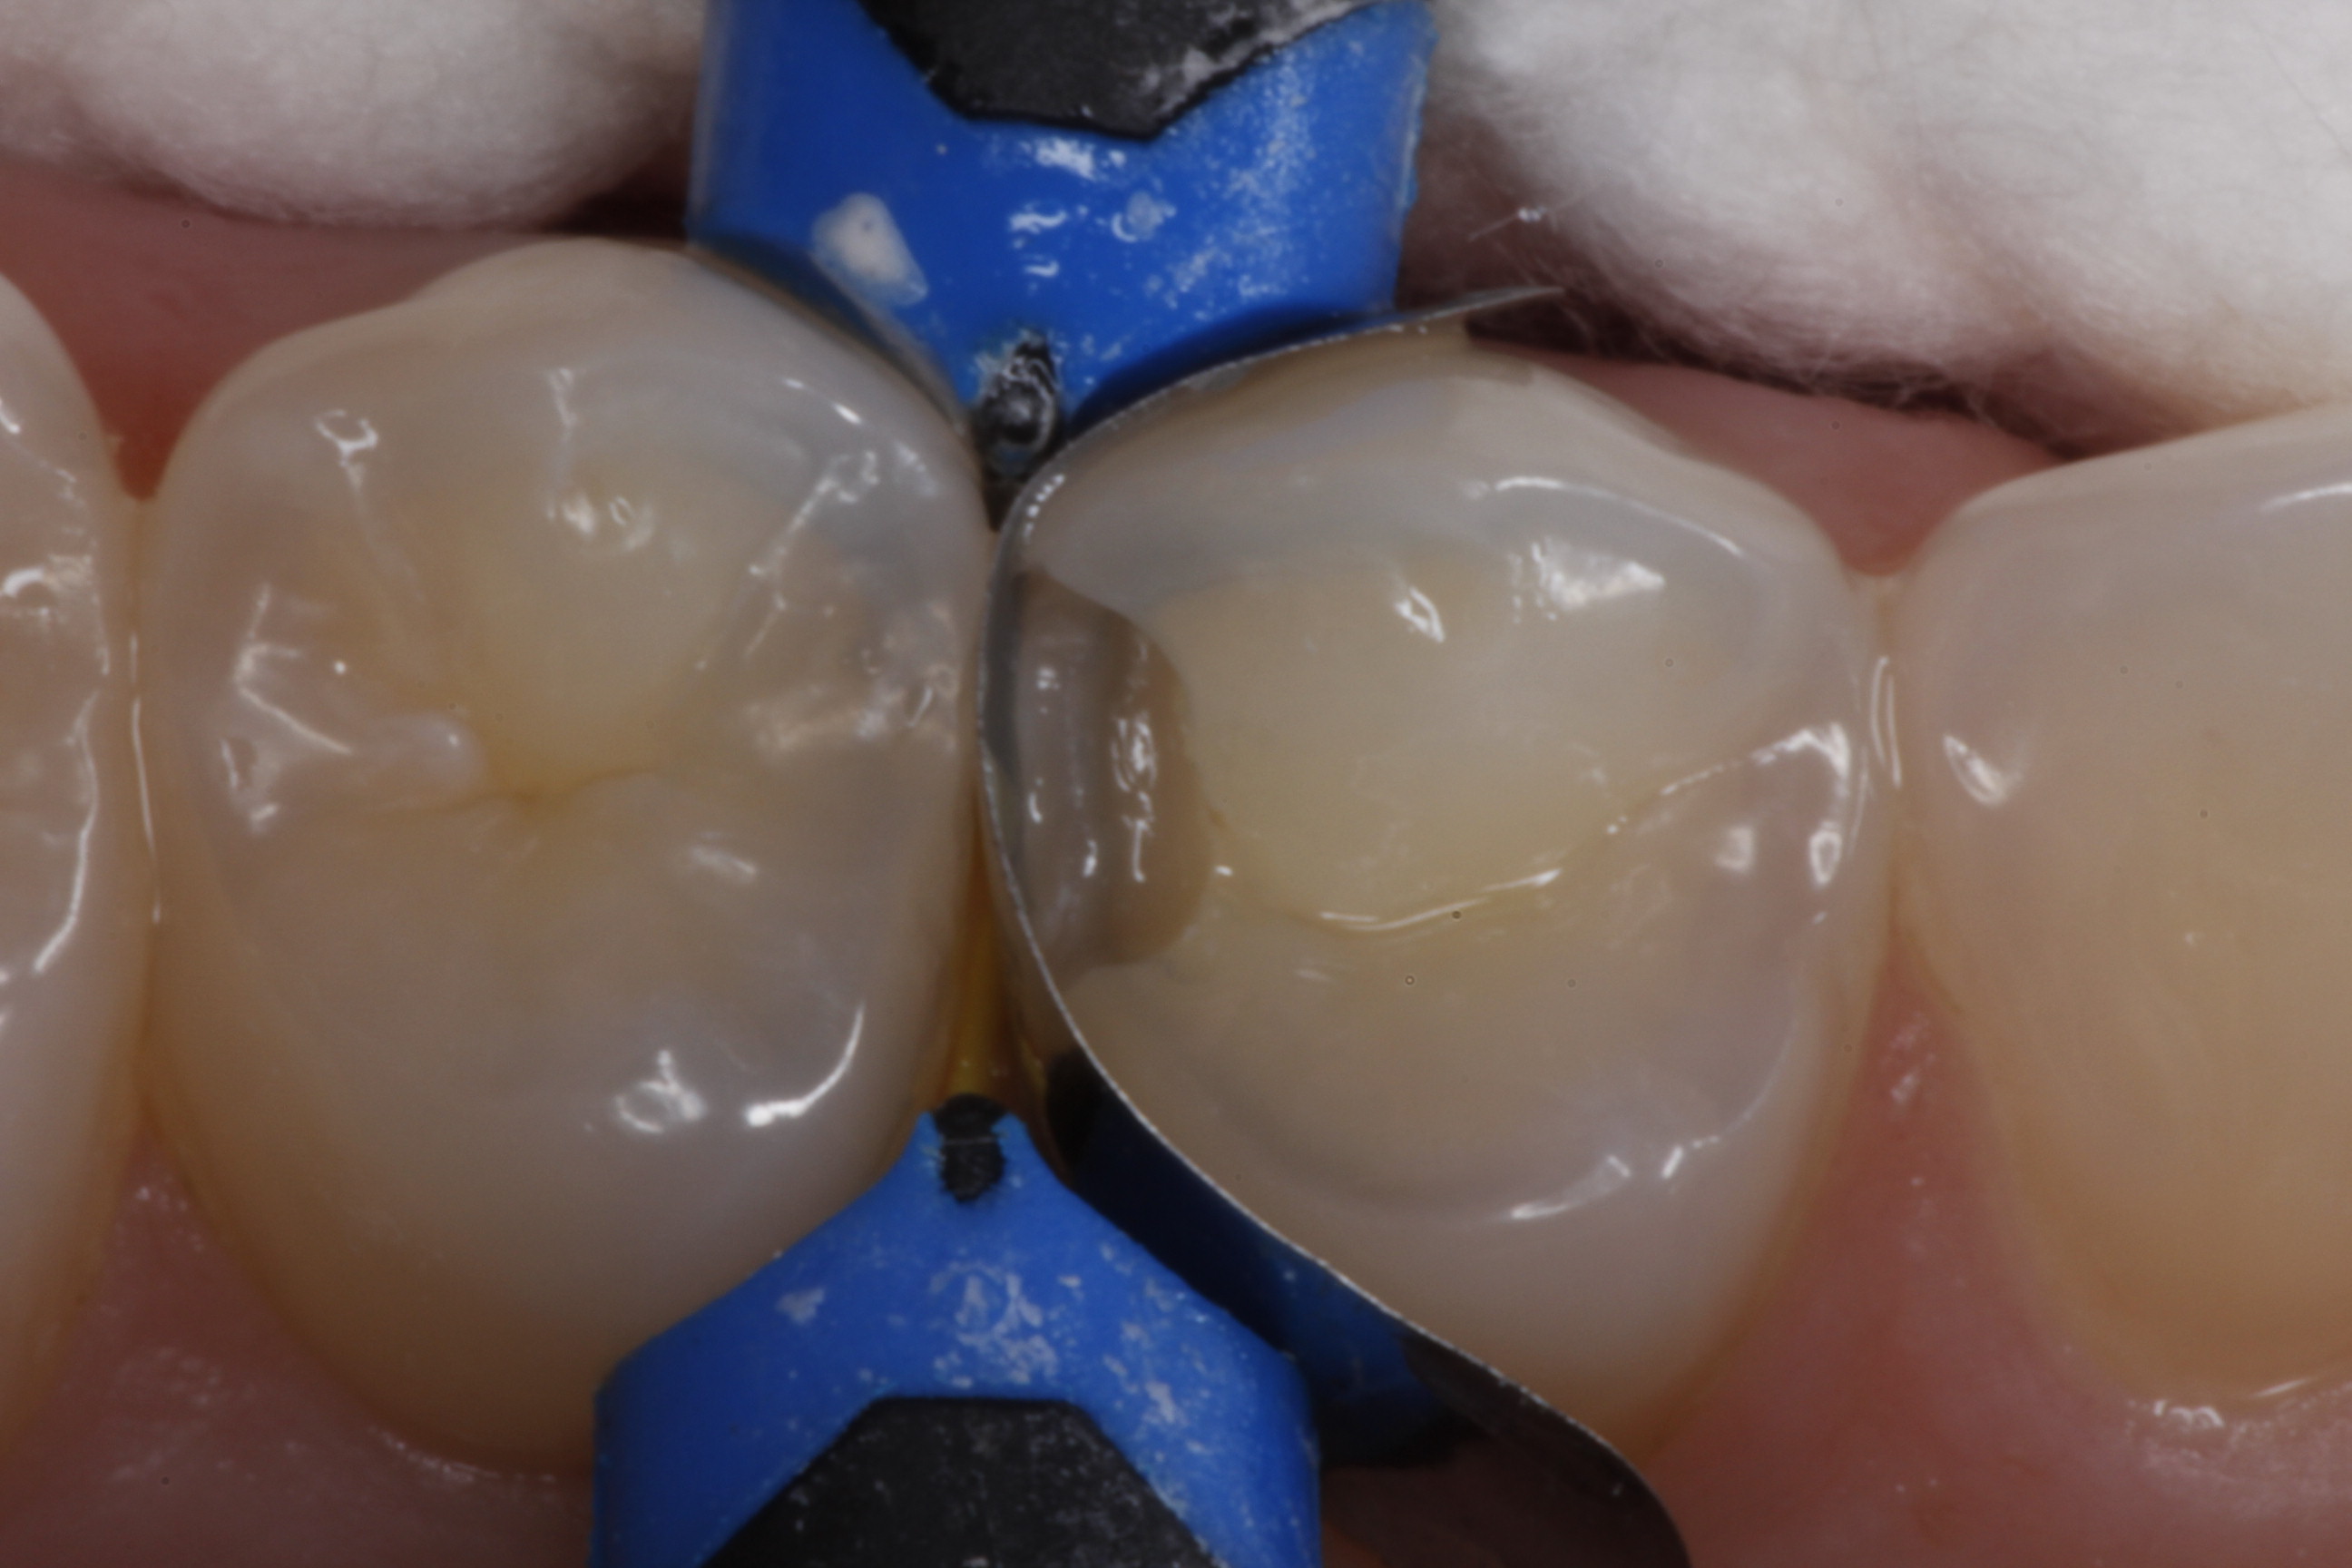

Fig 26. A mesial-occlusal cavity preparation on tooth No. 3 is shown after isolation and placement of a sectional matrix.

Figure 26